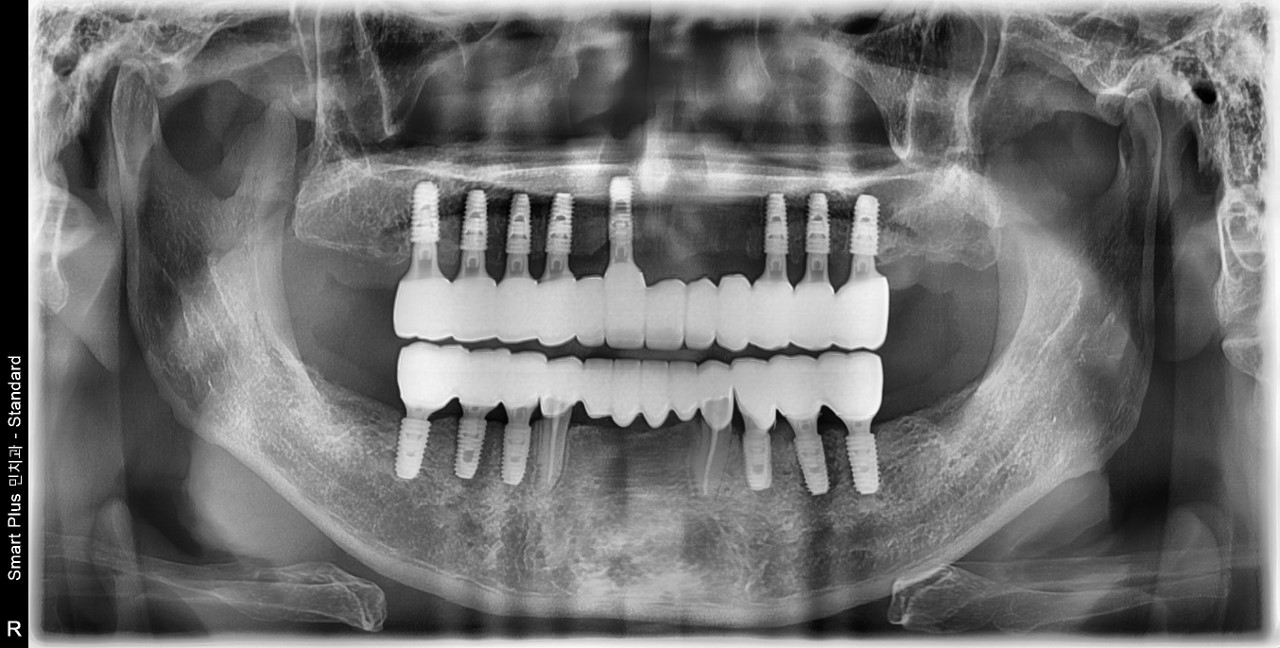

IMPLANT CASE BEFORE AND AFTER

임플란트 치료 전후

구강과 안모의 조화, 기능을 면밀하게 파악하여 1:1 맞춤 시술로 진행하는 안전하고 정확한 민치과의원의 임플란트 치료